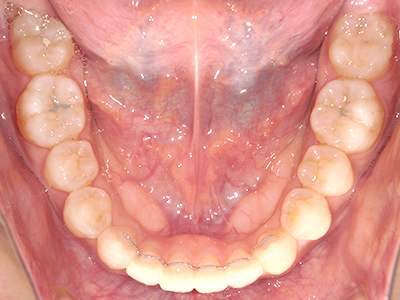

【4】矯正治療

矯正装置を装着し、調整しながら少しずつ歯を移動させ、歯並びを整えていきます。

【5】保定期間

治療後の一定期間は、定期的にチェックを行い経過観察していきます。